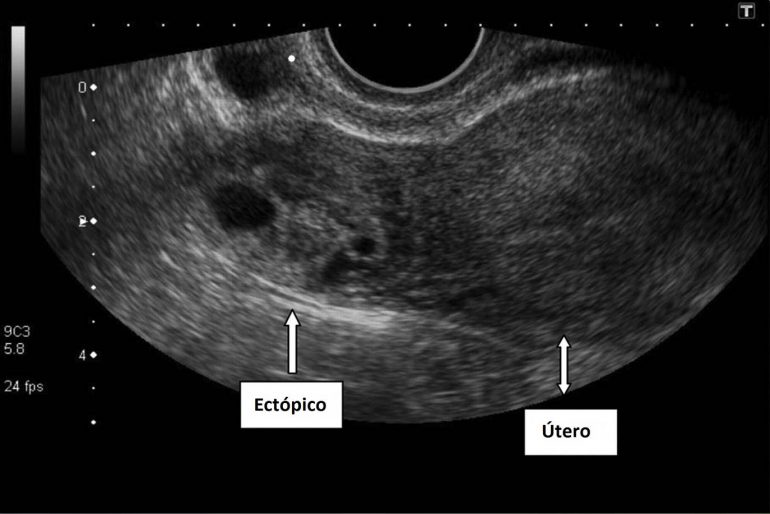

Aplicaciones en obstetricia y ginecología:.

que es una ultrasonografia La ultrasonografía eus ofrece una imagen. La denominación ecografía o ultrasonido se refiere a un procedimiento que emplea ondas sonoras de alta frecuencia para ver el interior del cuerpo, colocando un transductor o. Una ecografía, también conocida como sonograma, es una prueba de diagnóstico por imagen que utiliza ondas sonoras (ultrasonido) para crear imágenes de órganos,. La ultrasonografía es un método de diagnóstico por imagen que utiliza un transductor para emitir. Un ultrasonido de la mama es una técnica de imágenes que se utiliza comúnmente para detectar tumores y otras anomalías en los senos. Aplicaciones en obstetricia y ginecología:. El ultrasonido es un examen médico no invasivo que ayuda a los médicos a diagnosticar y tratar condiciones médicas. Descubre qué es un ultrasonido o ecografía y cuáles son sus usos en el cuidado de la salud.

La detección por ultrasonidos puede tener una capacidad limitada para